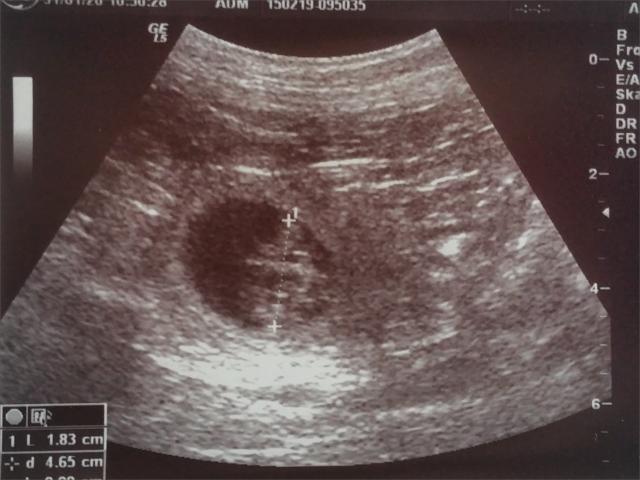

31.01.2020: Wir waren heute beim Ultraschall mit Gina

und haben kleine Babys im Bauch gesehen! :-)

Somit erwarten wir unseren A2-Wurf Anfang März! Bei

Interesse bitte melden! :-)